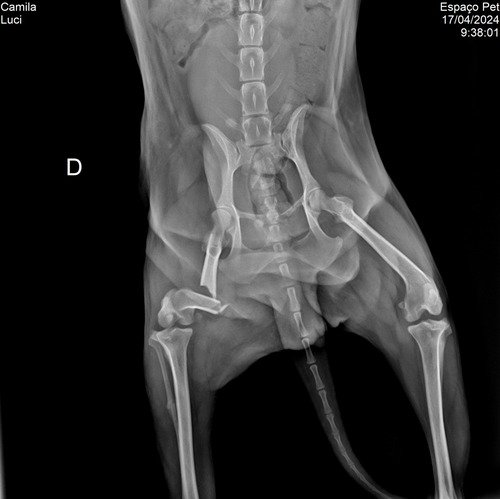

Nossa cachorrinha foi atropelada e vai precisar fazer uma cirurgia na patinha, o valor total é R$ 2.200,00 ver tudo

Nossa cachorrinha foi atropelada e vai precisar fazer uma cirurgia na patinha, o valor total é R$ 2.200,00